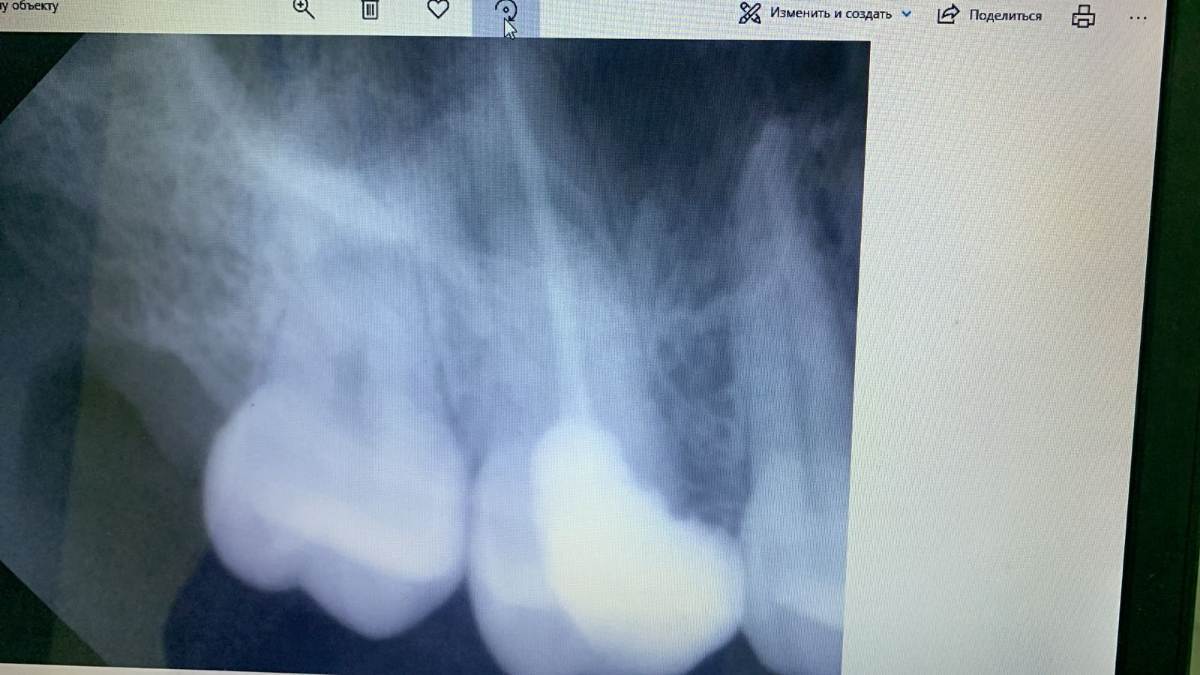

Марина Б Опубликовано 13 октября, 2025 Поделиться Опубликовано 13 октября, 2025 Добрый день! Прошу посмотреть снимок, есть ли воспаление зубных каналов (опломбированный зуб, но он у меня раскололся сейчас)? Нужно лечить? Один стоматолог не увидел воспаление, другой говорит, что видит воспаление и надо "проходить", лечить зубные каналы. Кому верить? Ссылка на комментарий

red_butler Опубликовано 13 октября, 2025 Поделиться Опубликовано 13 октября, 2025 34 минуты назад, Марина Б сказал: Здравствуйте! А по этим снимкам вообще не видно, есть ли воспаление? панорамный снимок плохого качества, а по прицелу скорее воспаление есть... 1 Ссылка на комментарий